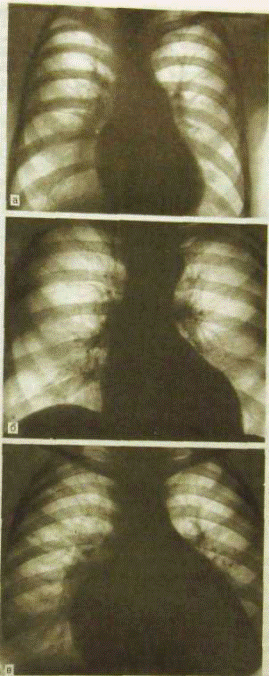

Форма тени сердца на рентгенограммах в прямой проекции

а — митральная; б — аортальная; в — трапециевидная (треугольная).